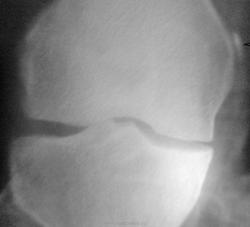

Пол пациента: Женский пол Тип патологии: Другое Область исследования: Скелетно-мышечная система Методы исследования: Rg Доброго времени суток! Коллеги, подскажите, что это может быть возле медиального надмыщелка бедренной кости? Пациентку 65 лет направил хирург с ДОА. Заранее спасибо. https://radiomed.ru/sites/default/files/styles/case_slider_image/public/user/12/12.foto0170-1.jpg?itok=EaLMu7dQ https://radiomed.ru/sites/default/files/styles/case_slider_image/public/user/12/13.foto0174.jpg?itok=p2Fa3XXR ID:24113 Пнд, 29/10/2012 - 23:01 #1 Almo Не на сайте Был на сайте: 9 часов 51 минут назад Зарегистрирован: 28.09.2008 - 18:50 Публикации: 8256 Тень Штида( внутренный мыщелок бедра). Пнд, 29/10/2012 - 23:02 #2 Андрей Юрьевич Не на сайте Был на сайте: 6 дней 14 часов назад Зарегистрирован: 16.11.2008 - 22:16 Публикации: 18098 Пеллегрини - Штиды болезнь http://www.radiomed.ru/publications/kss-pellegrini-shtida-bolezn Хотя в наше время считалось, что не болезнь это, а так, синдром. Андрей Юрьевич Пнд, 29/10/2012 - 23:05 #3 И.Бондаренко Не на сайте Был на сайте: 2 дня 7 часов назад Зарегистрирован: 13.09.2011 - 22:55 Публикации: 9206 +1 Втр, 30/10/2012 - 05:58 #4 Петр Николаевич Не на сайте Был на сайте: 3 года 10 месяцев назад Зарегистрирован: 15.03.2011 - 13:22 Публикации: 150 Болезнь Пеллегрини - Штида +1 Втр, 30/10/2012 - 19:31 #5 maker4ik Не на сайте Был на сайте: 8 лет 7 месяцев назад Зарегистрирован: 19.10.2011 - 17:49 Публикации: 2682 Плюсую к Пеллегрини-Штида.

Тень Штида( внутренный мыщелок бедра).

Пеллегрини - Штиды болезнь http://www.radiomed.ru/publications/kss-pellegrini-shtida-bolezn Хотя в наше время считалось, что не болезнь это, а так, синдром.